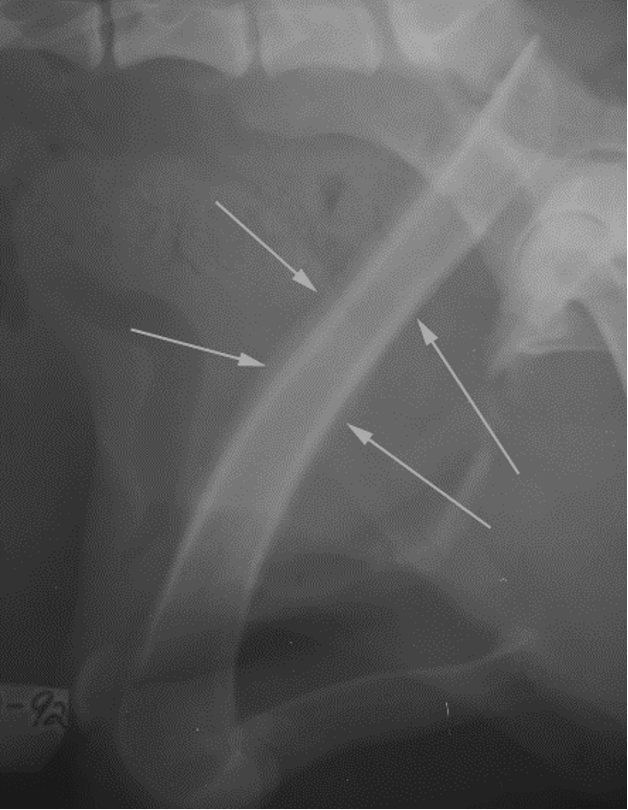

hypertrophic osteopathy signalment

middle to older dog

secondary to thoracic or abdominal dz/mass

spares small bones of carpus and tarsus

starts from MC/MT bones and goes up the leg symmetrically and bilateral

NO lysis but LOTs of periosteal rxn

AGG lesion

Hypertrophic Osteopathy